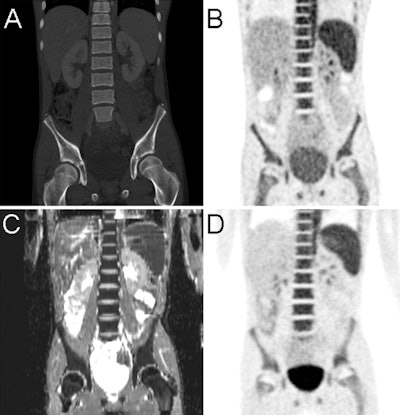

Images are of a 14-year-old patient with non-Hodgkin's lymphoma and bone marrow infiltration. PET from PET/CT (B) and PET from PET/MRI (D) show increased bone marrow uptake, paralleled by diffusion restriction shown on the apparent diffusion coefficient map (C). CT (A) findings of the PET/CT examination were inconclusive. Images courtesy of Radiology.As expected, MRI's higher soft-tissue contrast was able to identify diagnostic information in lesions that were interpreted as negative with PET.

"Thus, relevant additional findings were detected in four patients at PET/MR imaging compared with PET/CT," the authors wrote.

Conversely, CT discovered multiple lung metastases in two patients with sarcoma, which were only partly visible with MRI. PET/MRI also upstaged two pediatric cancer patients and found recurrence in two other children, resulting in a possible change in patient management.